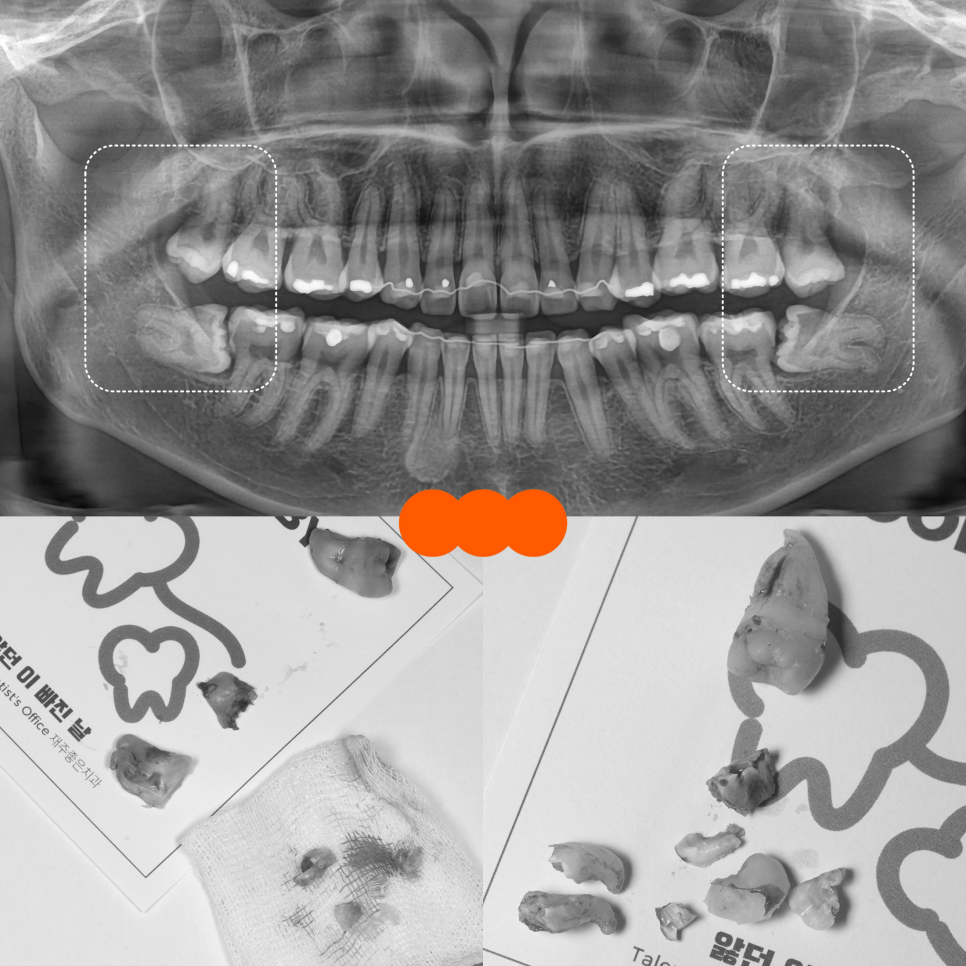

엑스레이를 보고 바로 느낀 건 ‘쉽지 않다’였어요.

잇몸 속에 묻혀 있는 형태는 육안으로 확인하기가 힘들어서 엑스레이를 통해 정확한 상태를 확인해 봤는데요.

위쪽은 똑바로 나있었지만 아래 사랑니가 모두 매복 되었고 뿌리가 두 갈래로 갈라져 있었으며, 끝이 많이 휘어 있는 형태였어요.

또, 뿌리 끝과 하치조신경관의 거리가 매우 가까웠는데요.

이런 경우, 발치하다가 하치조신경관이 손상되는 경우도 있어서 매우 조심해야 됩니다.

다행히 뿌리가 부러지지 않고 잘 나왔어요.

뿌리와 엑스레이를 보면서 잘 나온 것 같았지만, 더블 체크를 위해 엑스레이를 촬영했어요.

깔끔하게 제거된 것을 볼 수 있었어요.

오른쪽도 뿌리가 부러지지 않고 신경관의 손상 없이 깔끔하게 제거되었어요.